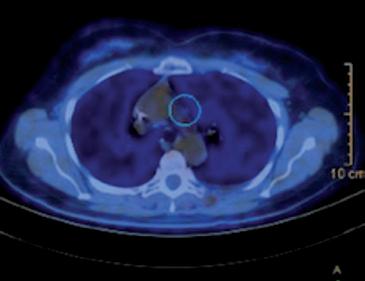

A giugno 2017 comparsa di metastasi ossea sternale e polmonari bilaterale alla PET/TC eseguita per persistenza di algie sternali.

Prosegue con la terapia di mantenimento con pertuzumab, trastuzumab e letrozolo fino a ottobre 2022, quando viene interrotta per progressione linfonodale e polmonare di malattia alla PET/TC di rivalutazione (figura 2).

Da dicembre 2022, considerando i dati dello studio DESTINY-Breast034,5, viene avviata terapia con T-DXd 5,4 mg/kg q21 ottenendo risposta metabolica completa alla rivalutazione PET/TC di marzo 2023 (figura 3). Ad aprile 2024 terapia ancora in corso (16 somministrazioni ricevute).

Figura 2. PET/TC con FDG alla progressione di malattia prima dell’avvio di T-DXd.

Figura 3. Prima rivalutazione PET/TC con FDG in corso di T-DXd.